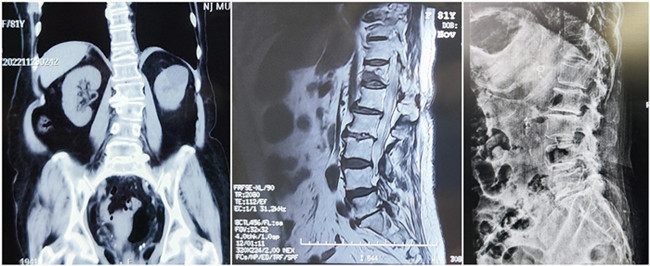

入院診斷:胸椎壓縮性骨折(T12)(主診斷);腰椎滑脫;腦梗死;高血壓1級(jí);糖尿病。

*患者術(shù)前影像

王伯堯主任帶領(lǐng)其醫(yī)療團(tuán)隊(duì)通過與患者的詳細(xì)溝通與交流,綜合評(píng)估椎體成形術(shù)治療超高齡椎體壓縮性骨折患者的安全性更高,以及病患病情的復(fù)雜性,最終決定運(yùn)用智能化的手段,為患者制定個(gè)性化的手術(shù)方案,施行骨科機(jī)器人輔助下的T12經(jīng)皮椎體球囊擴(kuò)張成形術(shù)。